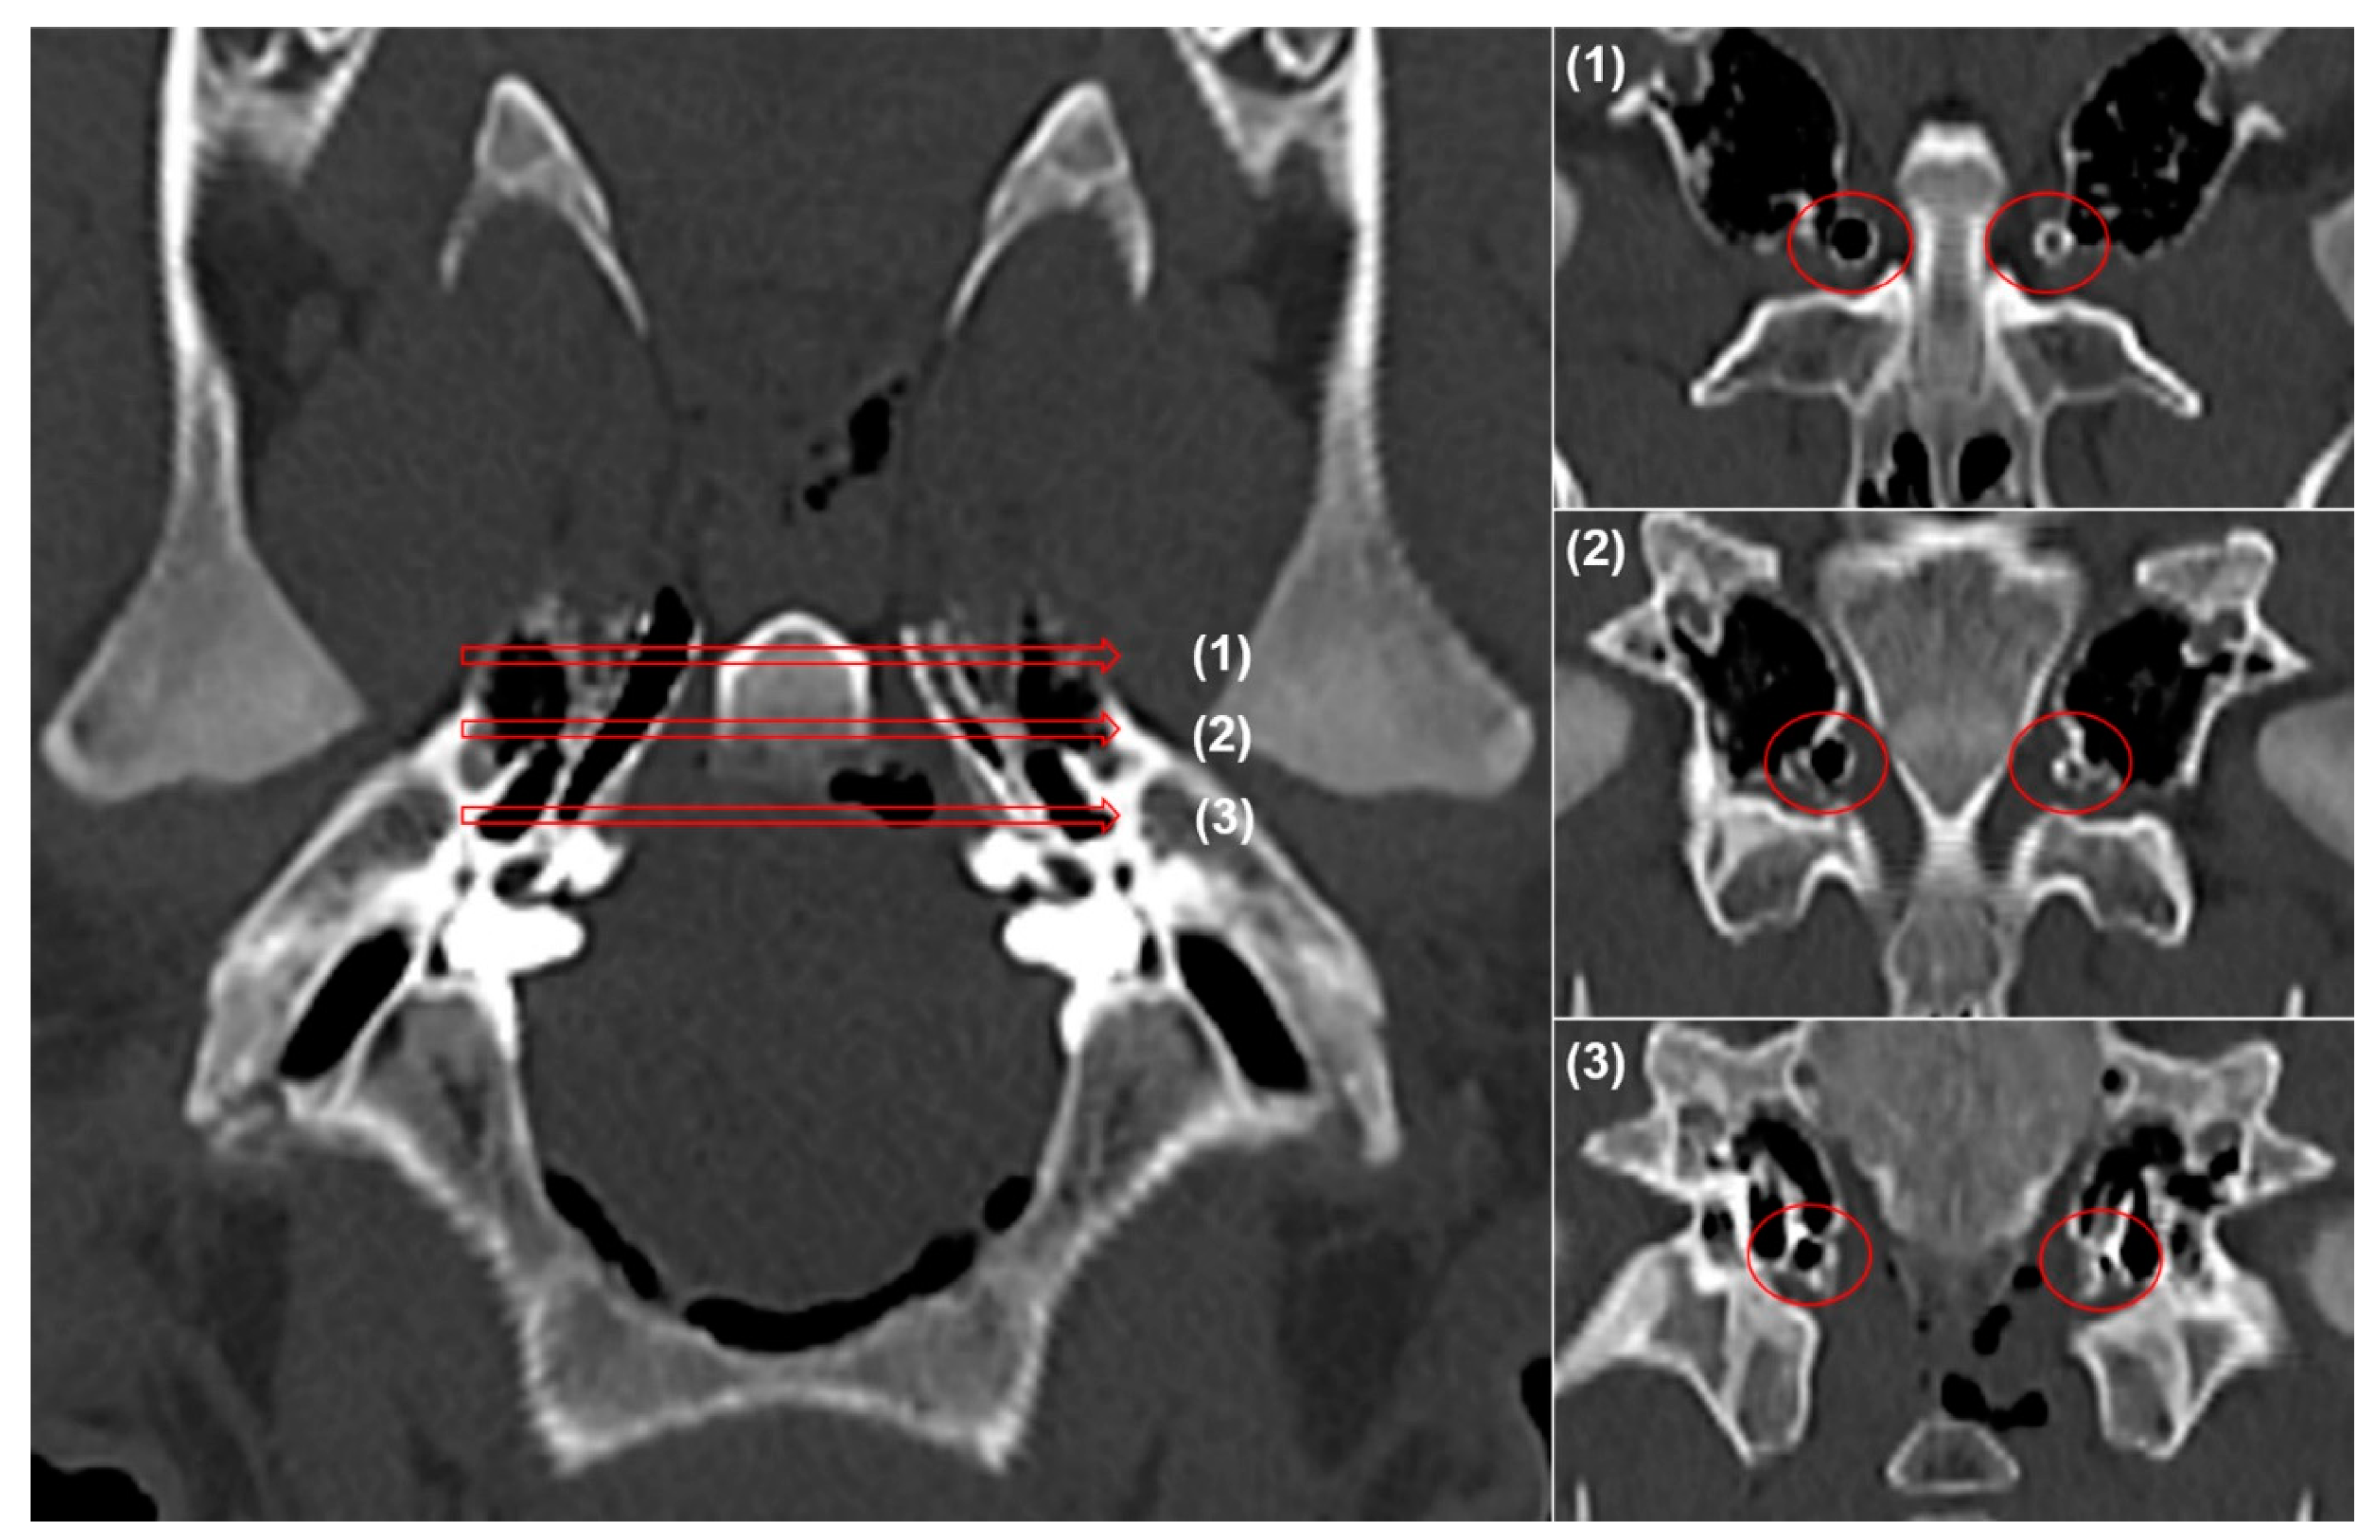

2.4. Computed Tomography